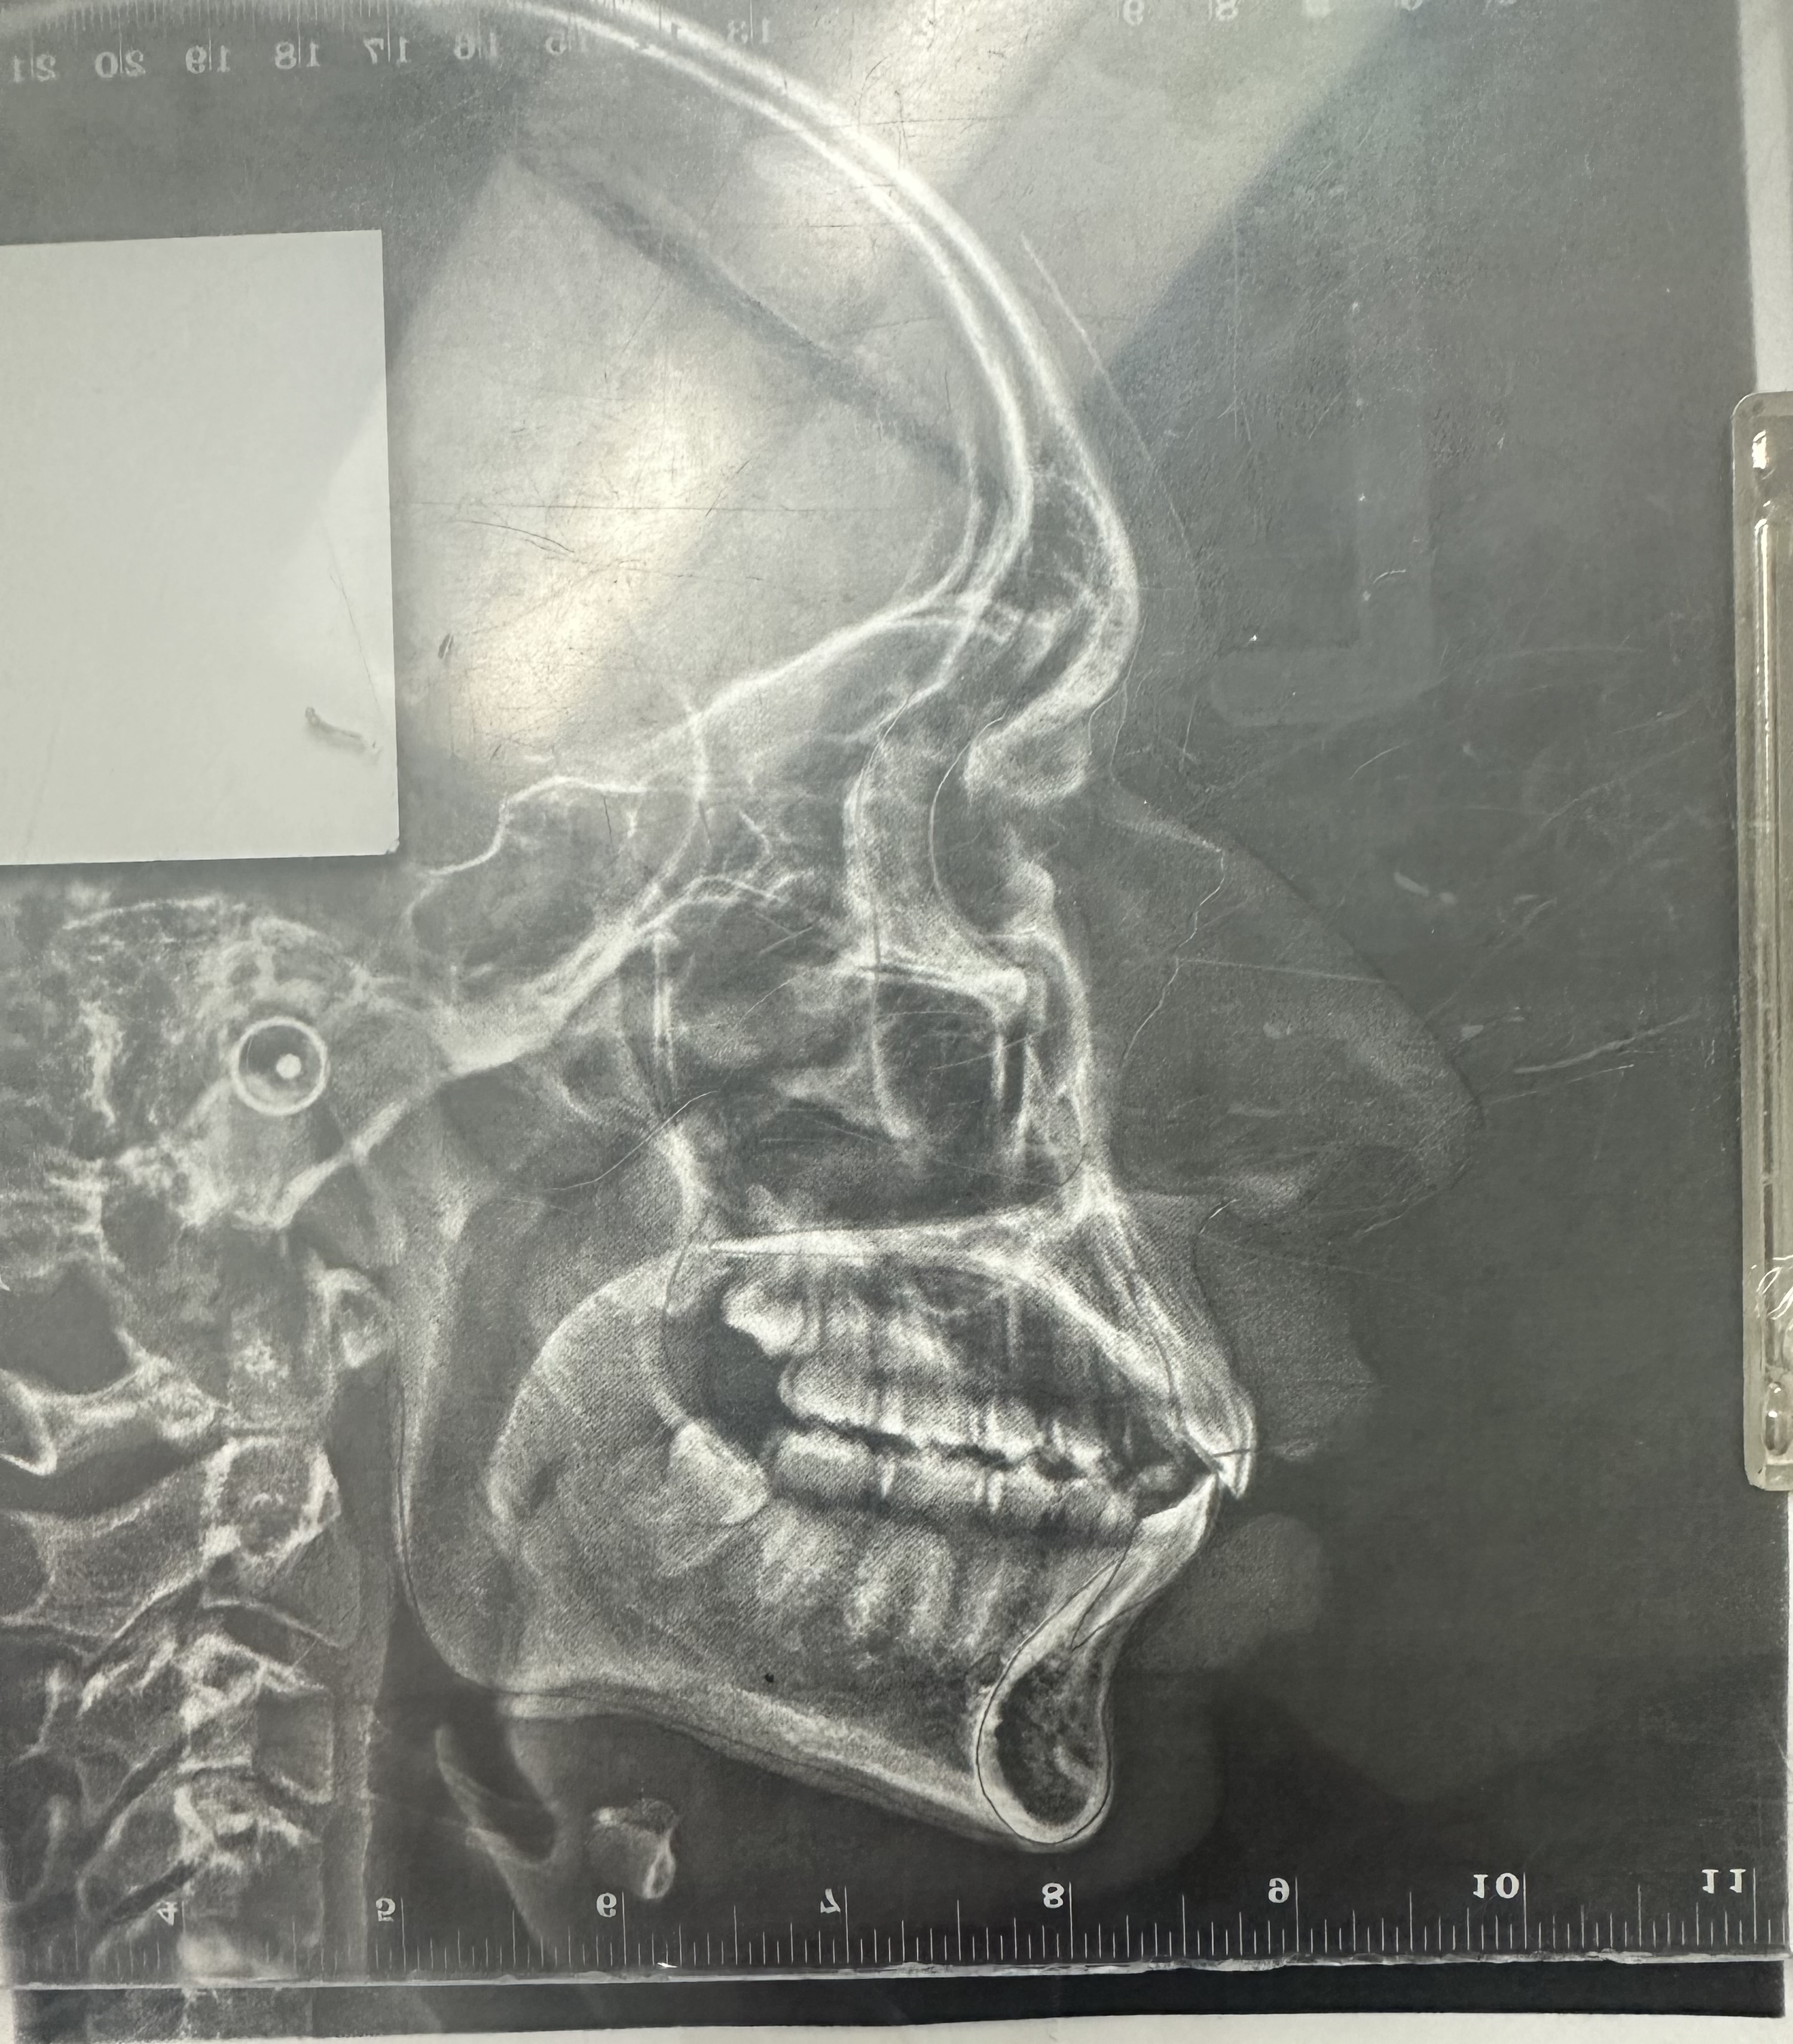

Over for my maxilla?

IMG 2697